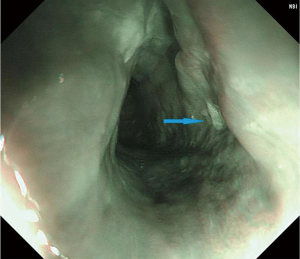

Upper gastrointestinal tract endoscopy disclosed a giant submucosal mass with a smooth surface that was located 18 to 40 cm from the incisors. Multiple biopsy specimens revealed inflamed mucosa with hyperaemia. There was no evidence of malignancy. Ultrasonic gastroscopy disclosed a giant protrusion of the esophagus located 18 cm from the incisors that originated from the submucous and was suspected to be a neurofibroma because of its homogeneous and hypoechoic lesion with clear margins. Distal esophagus and gastroesophageal junction was normal (Figures 1,2). A barium swallow showed a large intraluminal mass of the upper esophagus and compensatory dilatation of the proximal esophagus. A slightly irregular mucosal surface indicated a probable benign esophageal tumor (Figure 3). The patient underwent cervical, cardiac and abdominal ultrasound, which were unremarkable. Blood counts, biochemistry values and tumor markers levels were all found to be within normal limits.